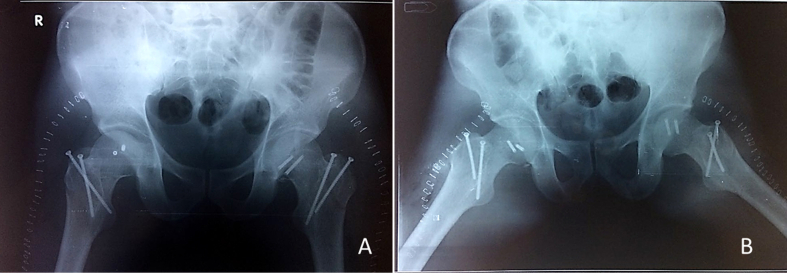

Fig. 4.

The fracture on both sides were reduced and fixed with headless Herbert screws through Ganz’s Trochanteric flip osteotomy.

Fig. 5.

Postoperative radiograph shows anatomical reduction of the fracture with congruous joints.